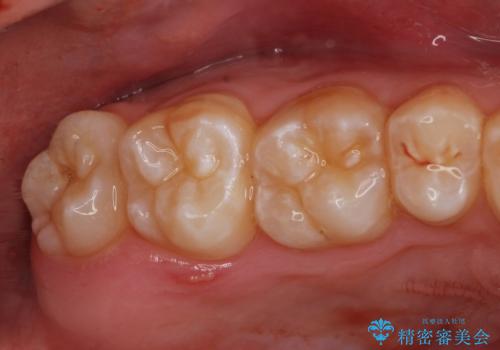

右下親知らず抜きたい。

- 右上下親知らずを抜きたいとの事で来院。

レントゲンを確認したとこと完全埋伏歯でした。

無事抜歯を行うことができました。